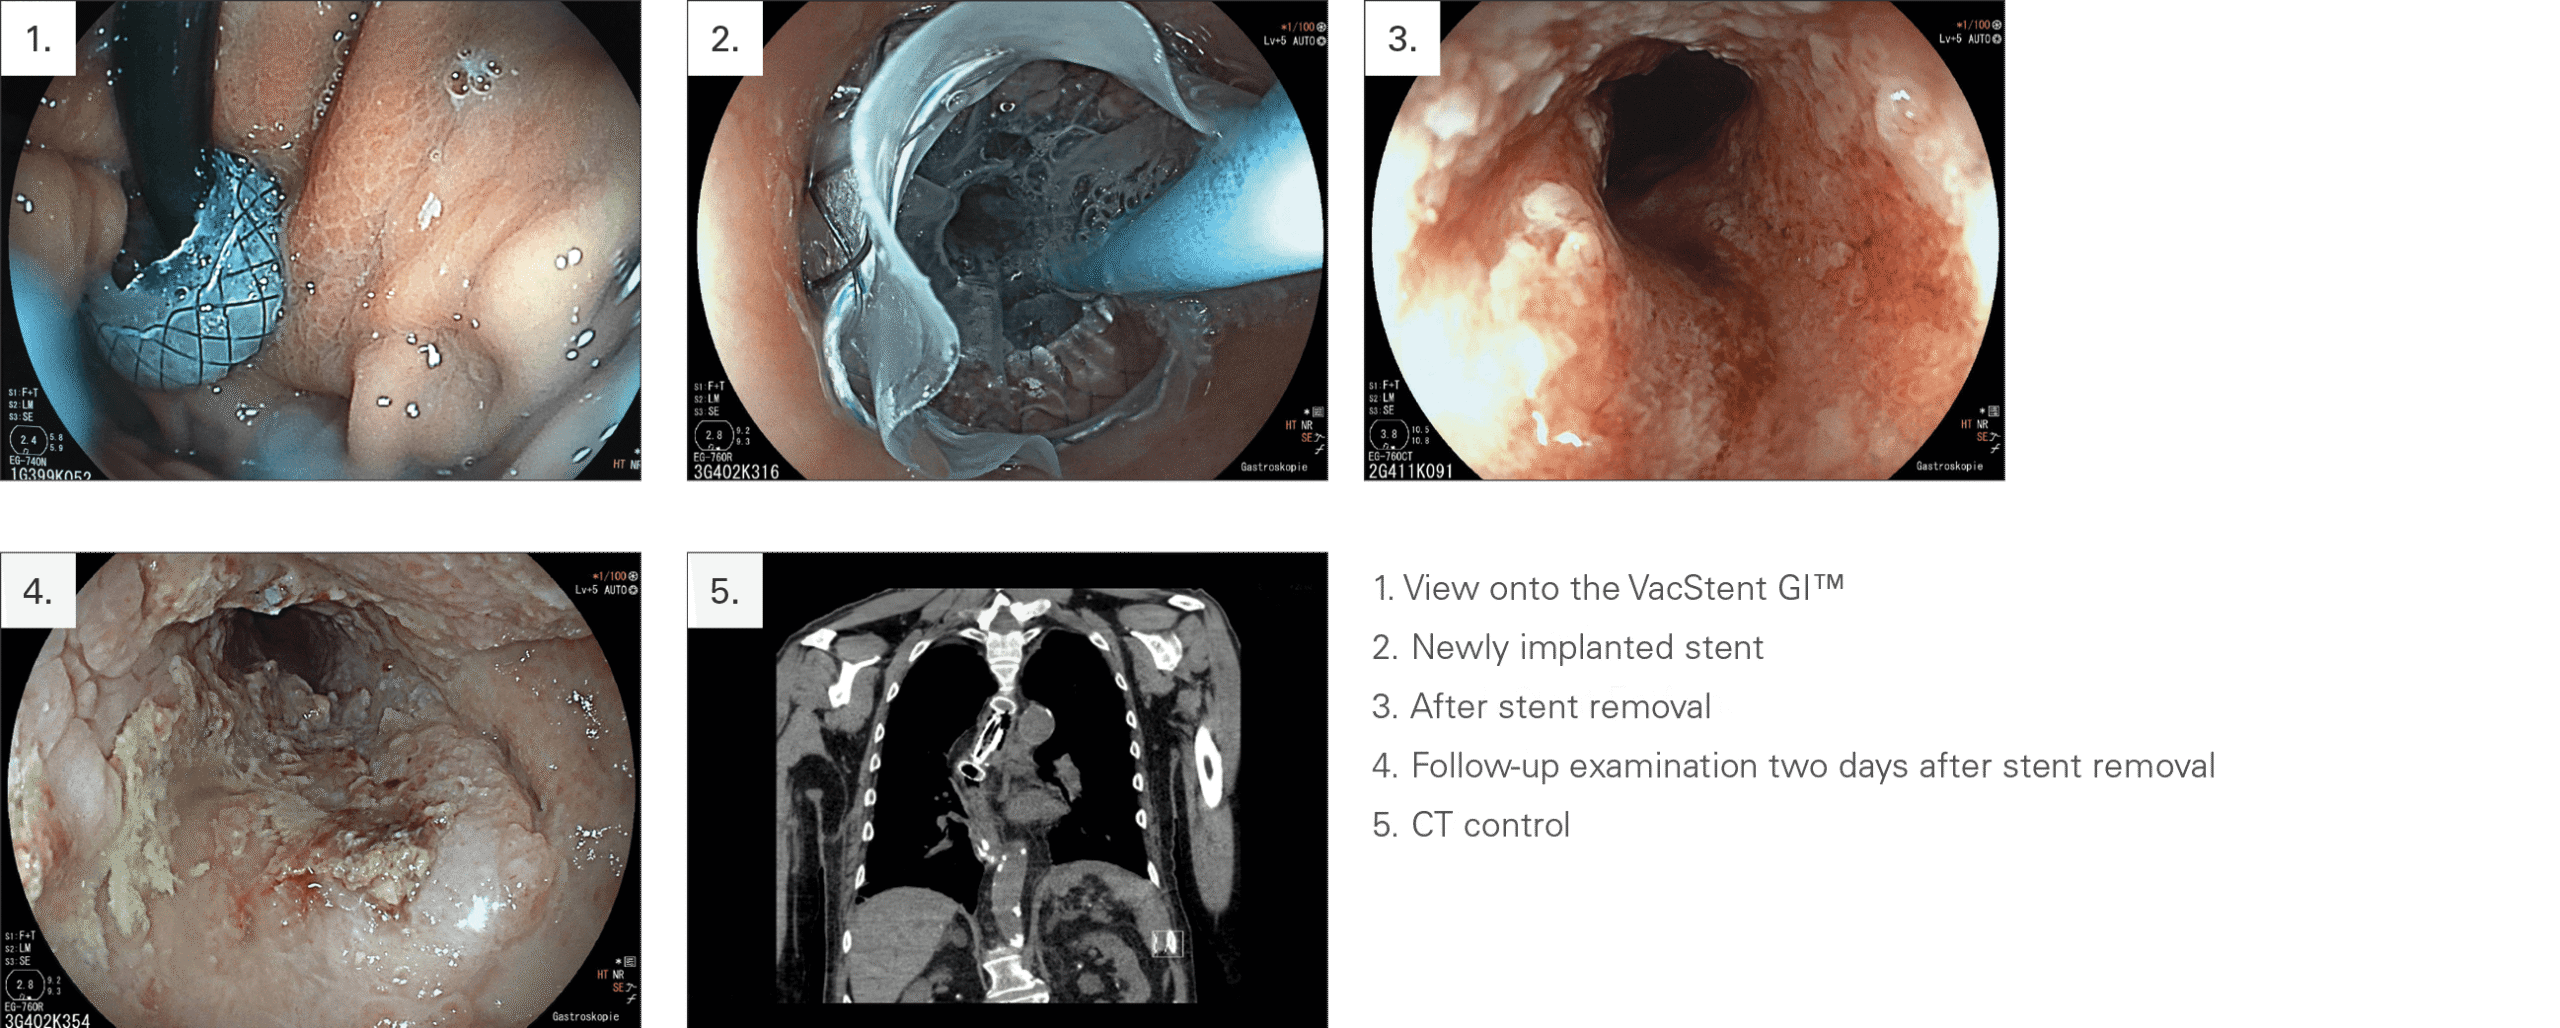

A CASE REPORT

“Combining the benefits of endoscopic vacuum therapy and covered stents for upper gastrointestinal tract leakage”

CLINICAL USE